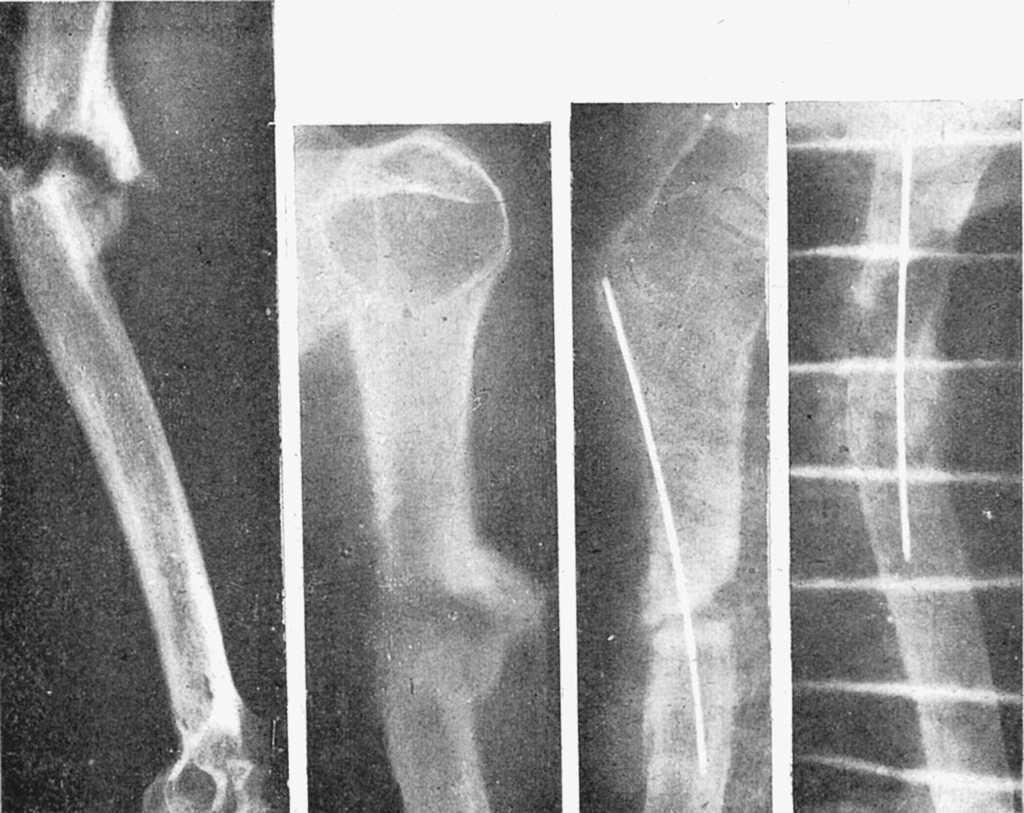

Figura 3. Fractura tercio medio tibia y peroné; enclavijamiento cerrado con un solo clavo; un tercer fragmento impide la exacta coaptación de fragmentos, obteniéndose, no obstante, una buena consolidación con predominio de callo periostal; se aprecia en la parte superior el orificio de la trepanación de entrada del clavo.

Figura 4. Enclavijamiento mixto en una pseudoartrosis de cúbito y radio, previo refrescamiento de fragmento. Fue utilizado alambre en cúbito por no disponer entonces de tallo suficientemente largo. La misma, una vez obtenida la consolidación.

Figura 5. Fractura doble, antebrazo; enclavijamiento cerrado con alambres.